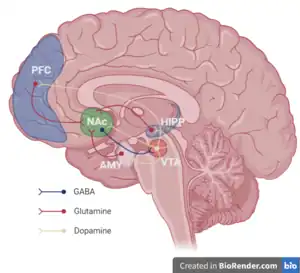

The mesocorticolimbic system (mesocorticolimbic circuit) refers to both the mesocortical and mesolimbic pathways.[3][12] Both pathways originate at the ventral tegmental area (VTA). Through separate connections to the prefrontal cortex (mesocortical) and ventral striatum (mesolimbic), the mesocorticolimbic projection has a significant role in learning, motivation, reward, memory and movement.[13] Dopamine receptor subtypes, D1 and D2 have been shown to have complementary functions in the mesocorticolimbic projection, facilitating learning in response to both positive and negative feedback.[14] Both pathways of the mesocorticolimbic system are associated with ADHD, schizophrenia and addiction.[15][16][17][18]

Mesolimbic pathway

Referred to as the reward pathway, mesolimbic pathway projects from the ventral tegmental area to the ventral striatum ( VTA → Ventral striatum (nucleus accumbens and olfactory tubercle).[17] When a reward is anticipated, the firing rate of dopamine neurons in the mesolimbic pathway increases.[19] The mesolimbic pathway is involved with incentive salience, motivation, reinforcement learning, fear and other cognitive processes.[6][16][20] In animal studies, depletion of dopamine in this pathway, or lesions at its site of origin, decrease the extent to which an animal is willing to go to obtain a reward (e.g., the number of lever presses for nicotine or time searching for food).[19] Research is ongoing to determine the role of the mesolimbic pathway in the perception of pleasure.[21][22][23][24]

Regulation

The ventral tegmental area and substantia nigra pars compacta receive inputs from other neurotransmitters systems, including glutaminergic inputs, GABAergic inputs, cholinergic inputs, and inputs from other monoaminergic nuclei. The VTA contains 5-HT1A receptors that exert a biphasic effects on firing, with low doses of 5-HT1A receptor agonists eliciting an increase in firing rate, and higher doses suppressing activity. The 5-HT2A receptors expressed on dopaminergic neurons increase activity, while 5-HT2C receptors elicit a decrease in activity.[35] The mesolimbic pathway, which projects from the VTA to the nucleus accumbens, is also regulated by muscarinic acetylcholine receptors. In particular, the activation of muscarinic acetylcholine receptor M2 and muscarinic acetylcholine receptor M4 inhibits dopamine release, while muscarinic acetylcholine receptor M1 activation increases dopamine release.[36] GABAergic inputs from the striatum decrease dopaminergic neuronal activity, and glutaminergic inputs from many cortical and subcortical areas increase the firing rate of dopaminergic neurons. Endocannabinoids also appear to have a modulatory effect on dopamine release from neurons that project out of the VTA and SNc.[37] Noradrenergic inputs deriving from the locus coeruleus have excitatory and inhibitory effects on the dopaminergic neurons that project out of the VTA and SNc.[38][39] The excitatory orexinergic inputs to the VTA originate in the lateral hypothalamus and may regulate the baseline firing of VTA dopaminergic neurons.[40][41]